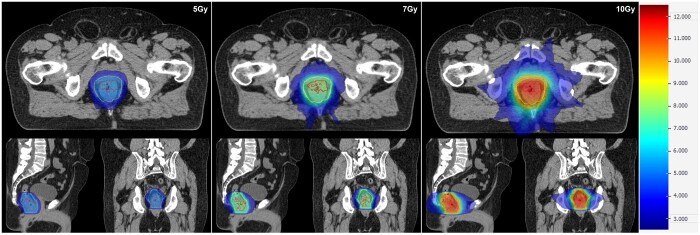

Methods: Ten patients previously treated with curative-intent standard long-course radiotherapy (50 Gy/25#) were re-planned. Boost target volumes (BTVs) were delineated semi-automatically using 40th centile intra-tumoural apparent diffusion coefficient value with expansions (anteroposterior 11 mm, transverse 7 mm, craniocaudal 13 mm). Biased-dosed combined plans consisted of a single-fraction volumetric modulated arc therapy flattening-filter-free (VMAT-FFF) boost (phase 1) of 5, 7, or 10 Gy before long-course VMAT (phase 2). Phase 1 plans were assessed with reference to stereotactic conformality and deliverability measures. Combined plans were evaluated with reference to standard long-course therapy dose constraints.

Results: Phase 1 BTV dose targets at 5/7/10 Gy were met in all instances. Conformality constraints were met with only 1 minor violation at 5 and 7 Gy. All phase 1 and combined phase 1 + 2 plans passed patient-specific quality assurance. Combined phase 1 + 2 plans generally met organ-at-risk dose constraints. Exceptions included high-dose spillage to bladder and large bowel, predominantly in cases where previously administered, clinically acceptable non-boosted plans also could not meet constraints.

Abstract Image